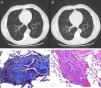

(A and B) An increase in the bronchoalveolar ratio is seen in the high definition CT scan during inspiration and expiration, a radiological sign suggestive of bronchiectasis and diffuse bronchiolectasis. No radiological signs of air trapping are observed. (C) Histological sample obtained from lung biopsy: Masson's trichrome stain; bronchiolar submucosal fibrosis is seen, along with the appearance of small scars. (D) Histological sample obtained from the lung biopsy: hematoxylin–eosin stain: bronchial obliteration can be observed.

We present the case of a male patient, 47 years of age, never-smoker, with a clinical history of hypertension on medical treatment, dyslipidemia on treatment with statins, Graves–Basedow disease treated 8 years ago with radioiodine (currently receiving replacement therapy) and Wilson's disease diagnosed 20 years ago, initially treated with zinc and for the past 2 years with penicillamine. He had a work history as a salesman, with no contact with toxic substances or poultry. The patient consulted due to dyspnea on exertion. An initial lung function study was performed which showed severe airflow limitation, so treatment with inhaled corticosteroids was initiated. A computed tomography (CT) scan of the chest was requested, along with complete lung function testing, revealing severe irreversible obstructive changes with air trapping and reduced carbon monoxide diffusing capacity (DLCO). Discrete bronchiectasis and diffuse bronchiolectasis were observed on the CT scan (Fig. 1). A sweat test to rule out cystic fibrosis was negative and an immunoglobulin study was normal. During the follow-up visit, respiratory failure was observed, so the decision was taken to admit the patient for further tests. On physical examination, oxygen saturation (breathing room air) was remarkable due to pulse oximetry of 88% without signs of labored breathing and normal pulmonary auscultation. The rest of the physical examination was normal. General clinical laboratory tests were unchanged and the chest CT was the same as before. In view of suspected drug-induced bronchiolitis, a biopsy was obtained from the lingula by anterior thoracotomy. After an uneventful post-operative period, the patient was discharged with domiciliary oxygen therapy. The final diagnosis from the pathology study was follicular bronchiolitis associated with constrictive bronchiolitis obliterans.